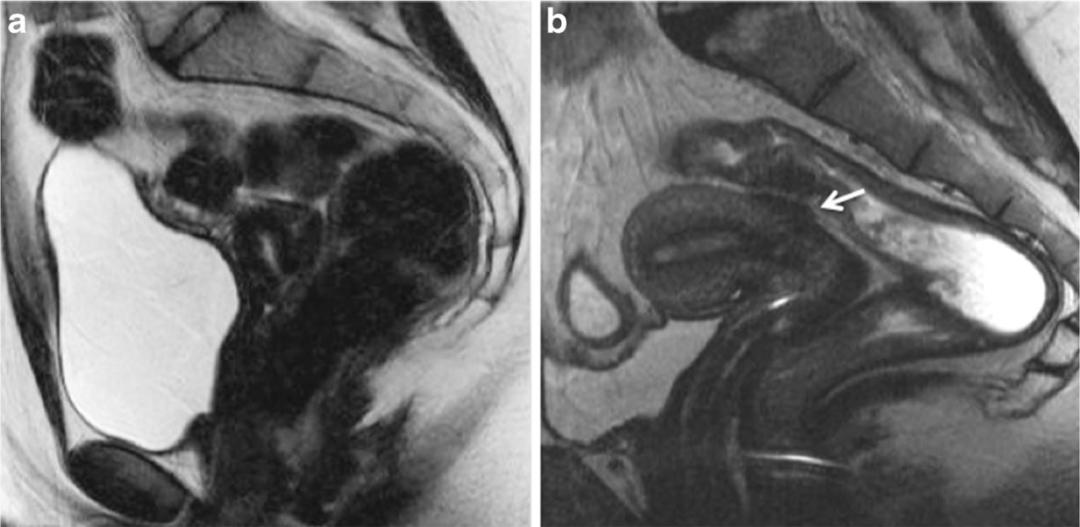

子宫内膜异位至膀胱,T2WI 矢状位显示膀胱顶上壁低信号结节,仔细观察其内超小高信号结节。

子宫内膜异位至右侧卵巢,T2WI 矢状位呈类圆形高信号,注意的是同时异位至道格拉斯窝及宫颈后区,T2WI 矢状位显示病灶呈低信号,中间夹杂更高信号结节,T1WI 轴位显示病灶多发高信号结节(提示多发出血点)